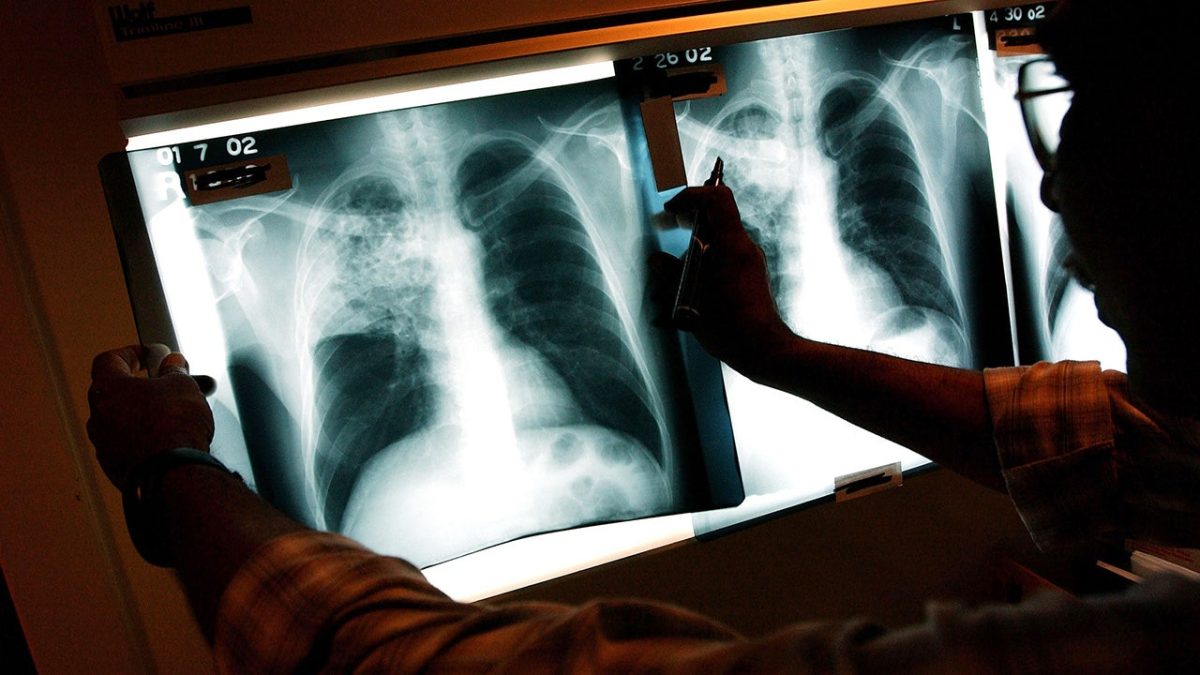

TB can present with various symptoms, or, at times, none at all. Those with active infections often experience persistent coughs—sometimes with blood, along with chest pain, fever, and fatigue.

It’s a bacterial infection primarily affecting the lungs, although it can target other organs too. The spread generally occurs from person to person, according to experts from Johns Hopkins.